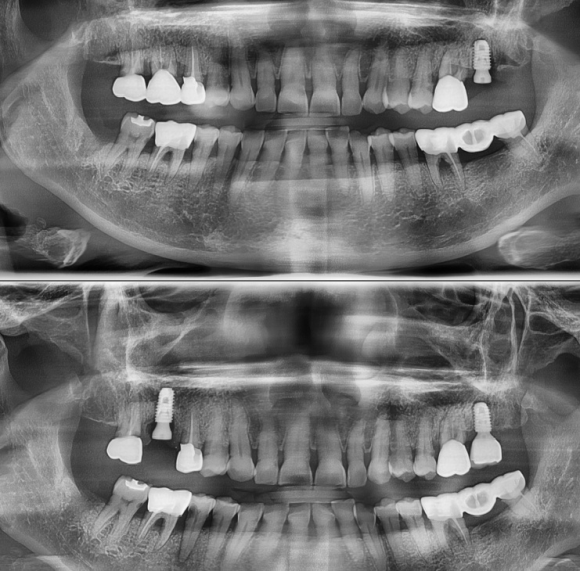

해당 환자의 경우

오랜기간 진행된 치아주변조직 염증의 확산으로 인하여

치아를 단단하게 잡아주어야 하는 뼈가 염증조직으로 대체되어

치아가 좌우 그리고 수직적으로 움직임이 심하고 통증이 발생하여

발치만이 유일한 치료가 되는 경우입니다.

발치 후 임플란트를 식립하고, Sinus 수술과 뼈이식을 함께 진행하였습니다.

이미 많이 진행된 병소의 치료에서는

그만큼 뼈가 많이 사라지고 염증이 퍼진 상태이기 때문에

완벽한 치료를 위해서는 그만큼 시간과 비용 그리고 노력이

경미할 때 진행하는 치료보다 더 들어가는 것을 명심해야 할 것입니다.

최소 6개월 후, 보철이 올라갈 예정입니다.